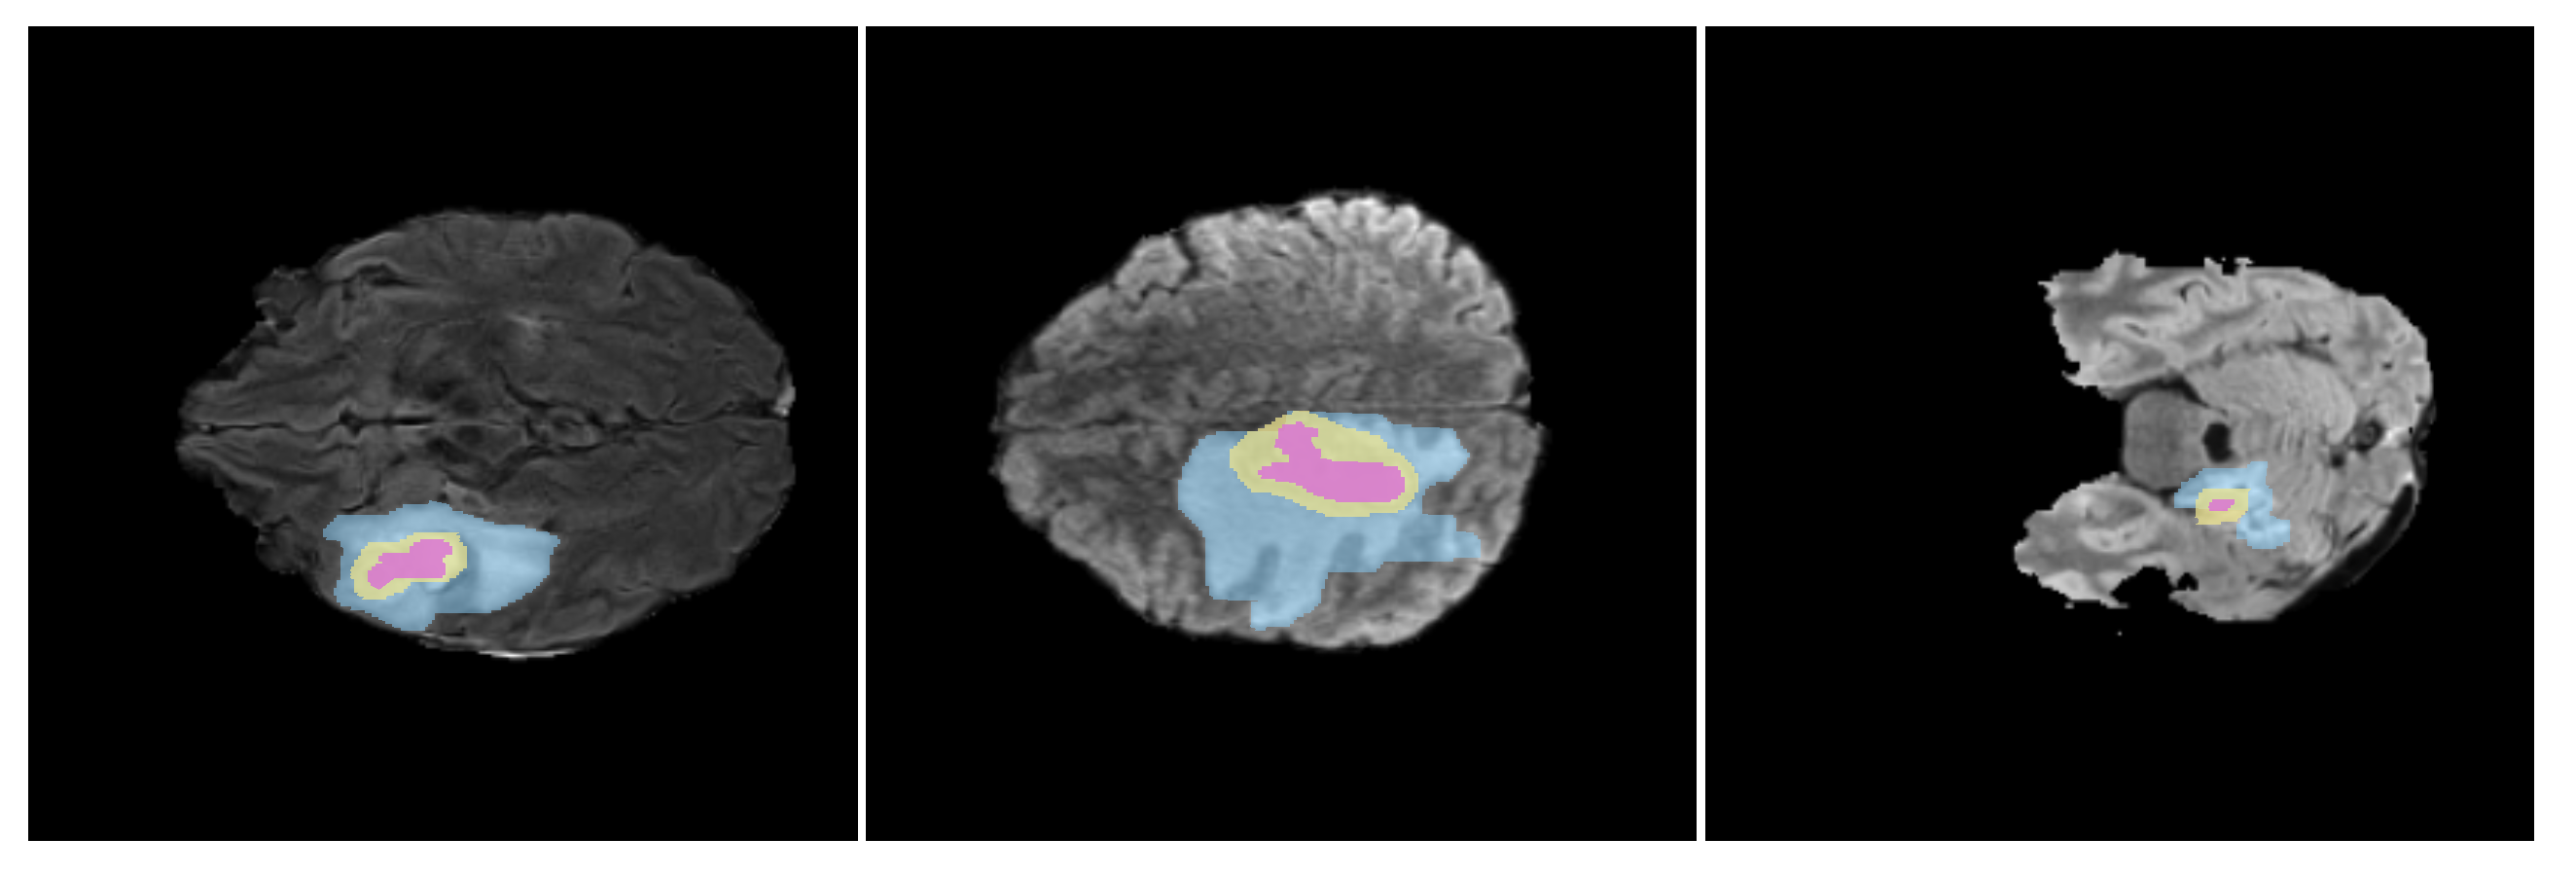

- Diana-Albelda, C.; Alcover-Couso, R.; García-Martín, Á.; Bescos, J. How SAM Perceives Different mp-MRI Brain Tumor Domains? In Proceedings of the IEEE/CVF Conference on Computer Vision and Pattern Recognition, Seattle, WA, USA, 17–21 June 2024; pp. 4959–4970. [Google Scholar]

- Diana-Albelda, C.; Alcover-Couso, R.; García-Martín, Á.; Bescos, J.; Escudero-Viñolo, M. GBT-SAM: A Parameter-Efficient Depth-Aware Model for Generalizable Brain tumour Segmentation on mp-MRI. arXiv 2025, arXiv:2503.04325. [Google Scholar]